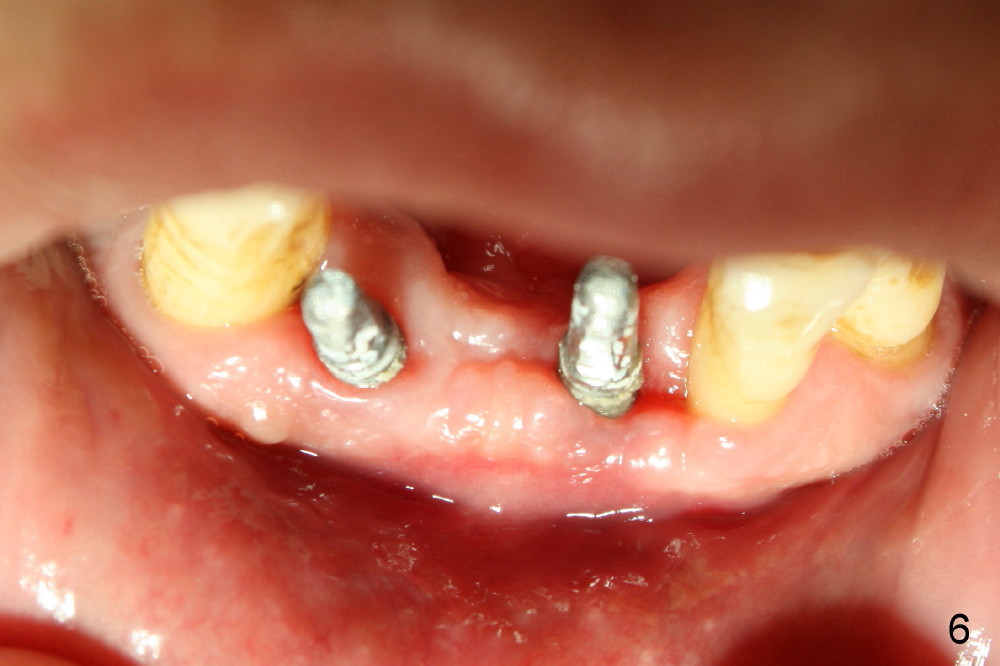

The patient plans to travel abroad. Two months ten days postop, the provisionals are removed for preparation for definitive FPD; the gingiva re-attaches to the implant at the site of #24 (Fig.6). The wound dehiscence is thought to be due to over placement of bone graft.